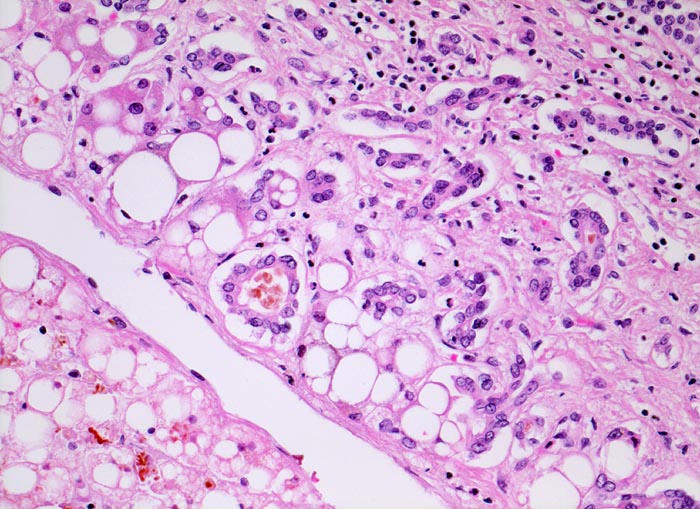

• Vollständiger feinknotiger zirrhotischer Umbau.

• Gemischtes portales, septales und intralobuläres Entzündungsinfiltrat.

• Floride sklerosierende alkoholische Steatohepatitis: Grobtropfige Verfettung von ca. 50% des Parenchyms.Neutrophile Granulozyten umgeben einzelne Hepatozyten (Satellitose). Wenig Apoptosekörperchen. Zahlreiche Mallory Körperchen und Megamitochondrien. Perivenuläre Maschendrahtfibrose.

• Hydropische Schwellung periportaler Hepatozyten.

• Canaliculäre Cholestase in einem Zirrhoseknoten.